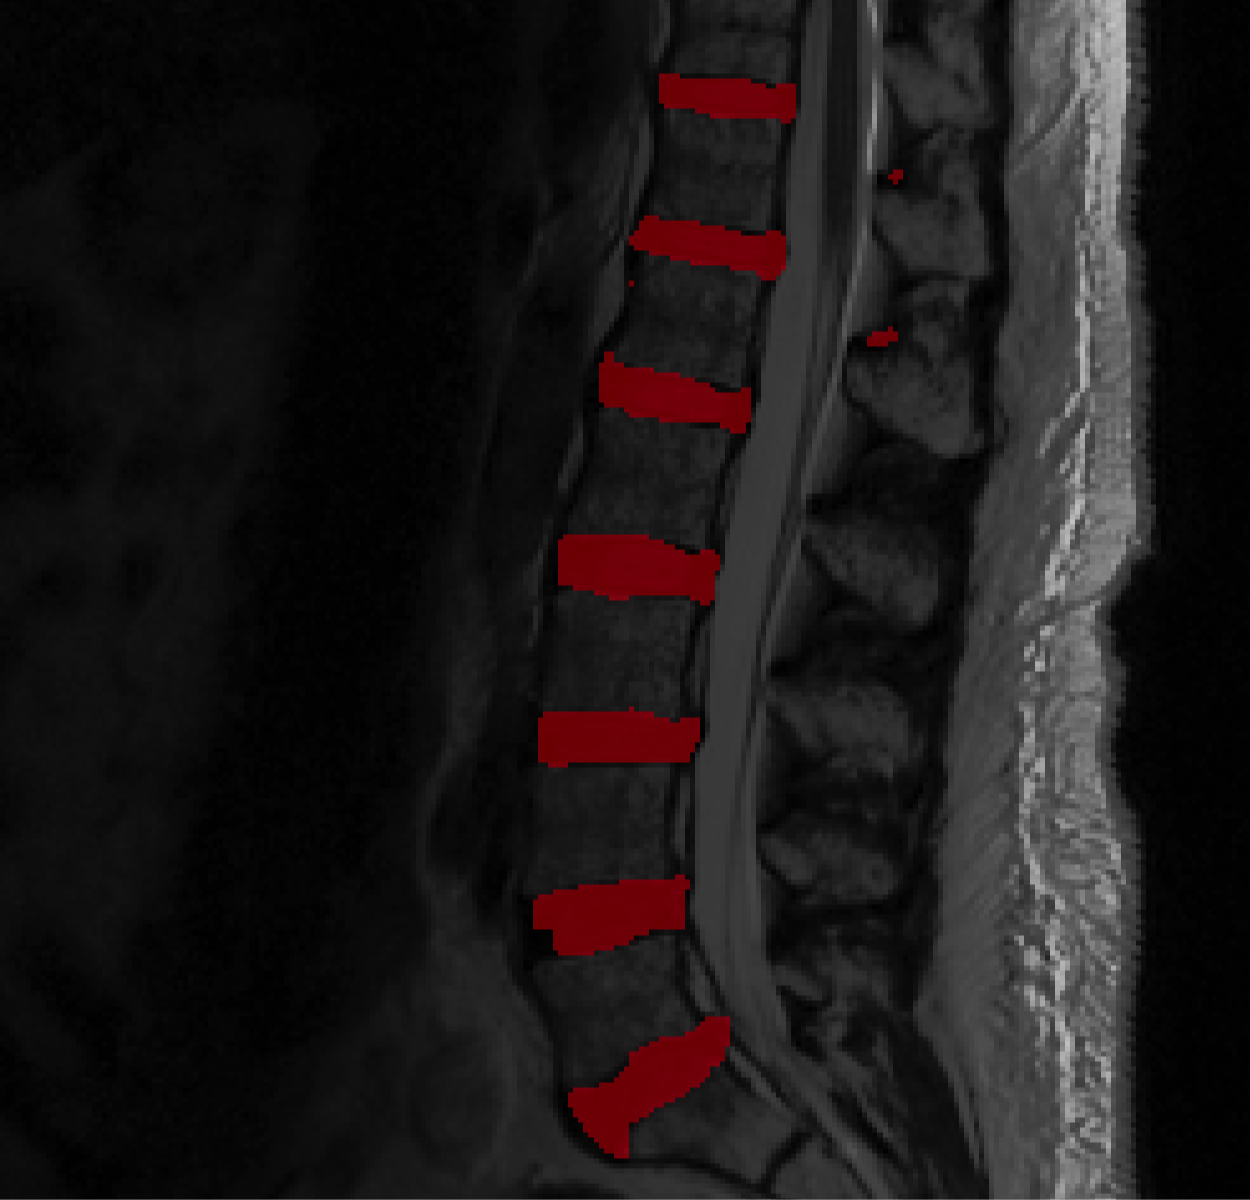

We used 40 scans for validation, none of which were in the training set to generate figures 6 and 7. Each of the 30 models trained, were used to segment the validation cohort of 40 cases, and Dice scores comparing algorithmic segmentations to human generated segmentations were recorded. Mean Dice scores for the entire validation datasets, generated by each model are presented in Table 2. To give the reader a qualitative assessment of how powerful extreme augmentation is, we show in figure 5, a mid-sagittal slice with segmentation overlays generated by models at 50x data augmentation. Dice scores, at augmentation levels 5x, 20x and 50x, for all training sets, are shown in figure 6. Likewise, figure 7 shows Dice scores generated by holding the data set size constant, and varying the level of augmentation. Only results from training datasets of sizes 1, 5 and 9 are shown.

Figures 3 and 4 along with table 1 indicate that more augmentation leads to lower training error, as does training with larger datasets. Figures 5 and 6 alongside Table 2, confirm this trend in the validation dataset. Thus, we may conclude that, for a given training dataset, a greater degree of augmentation leads to improved generalization accuracy. This is expected, given the long history of augmentation. What is surprising is how well augmentation can work. The top row of figure 3 (and figure 6) show that at 5x augmentation our trained model struggles to ‘learn’ how to segment disks. Bottom rows of the same figures show that with 50x augmentation, the situation is largely rectified. Perhaps, the most startling conclusion here is that a single scan, segmented by a human expert can be used by a deep machine learning algorithm to ‘learn’ how to segment inter-vertebral disks. Perhaps, this is true of other anatomical regions of interest as well. Of course, heavy augmentation (50x) is necessary to achieve this task (Fig 3, row 3). Figure 5 (c) shows that segmentation generated using a residual U-Net trained on a test case. While the segmentation in 5(c) is of poorer quality than that in 5(d) due to the presence of small noisy blobs in posterior to the spinal cord, it is still remarkable, given that the network was trained from exactly one delineated ‘scan’. All the disks are correctly localized and the delineation is comparable to human generated segmentation. This demonstrates the power of augmentation in training deep learning segmentation models.